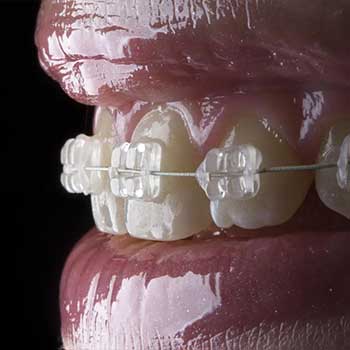

Ortodoncia

La ortodoncia corrige los defectos de la posición dental para mantener una sonrisa, perfecta y sana. Con la Dra. Lizeth Holguín podrás corregir la posición dental de esos defectos para mantener una boca sana y perfecta. Conoce las diferentes opciones que te brindaran nuestros especialistas y los diferentes tipos de tratamientos.